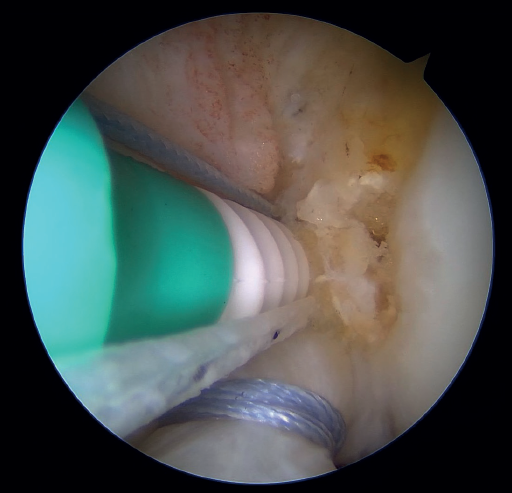

Once a good view of the central compartment is obtained, the area of the femoral footprint of the ACL is prepared to leave exposed bone, and microperforations are made in the medial wall of the lateral condyle to leave a bleeding bed to favor healing of the ligament (Figure 3). These microperforations can be made using specific instruments or with the implant punch. The advantage of using the punch is that the implant insertion site can be prepared at the same time, and only one instrument is used for the entire process (Figure 4). This step can be done after the suture has been prepared in the ligament, although doing it beforehand avoids the threads from standing in the way. The ideal point for fixation is just anterior to the native ACL footprint, although if the tear is partial or corresponds to Sherman I, it can be taken to the anatomical footprint without difficulty.

Outside the knee, the threads are loaded into a knotless anchor implant with a tape that will act as anterior reinforcement of the ACL when attached to the tibia. Once the implant has been loaded, it is inserted into the previously prepared site. This step is facilitated when viewing is made from the anteromedial portal, as it affords a better perspective of the zone (Figure 5). Once the implant has been inserted, the suture threads are cut at the level of the condylar wall.